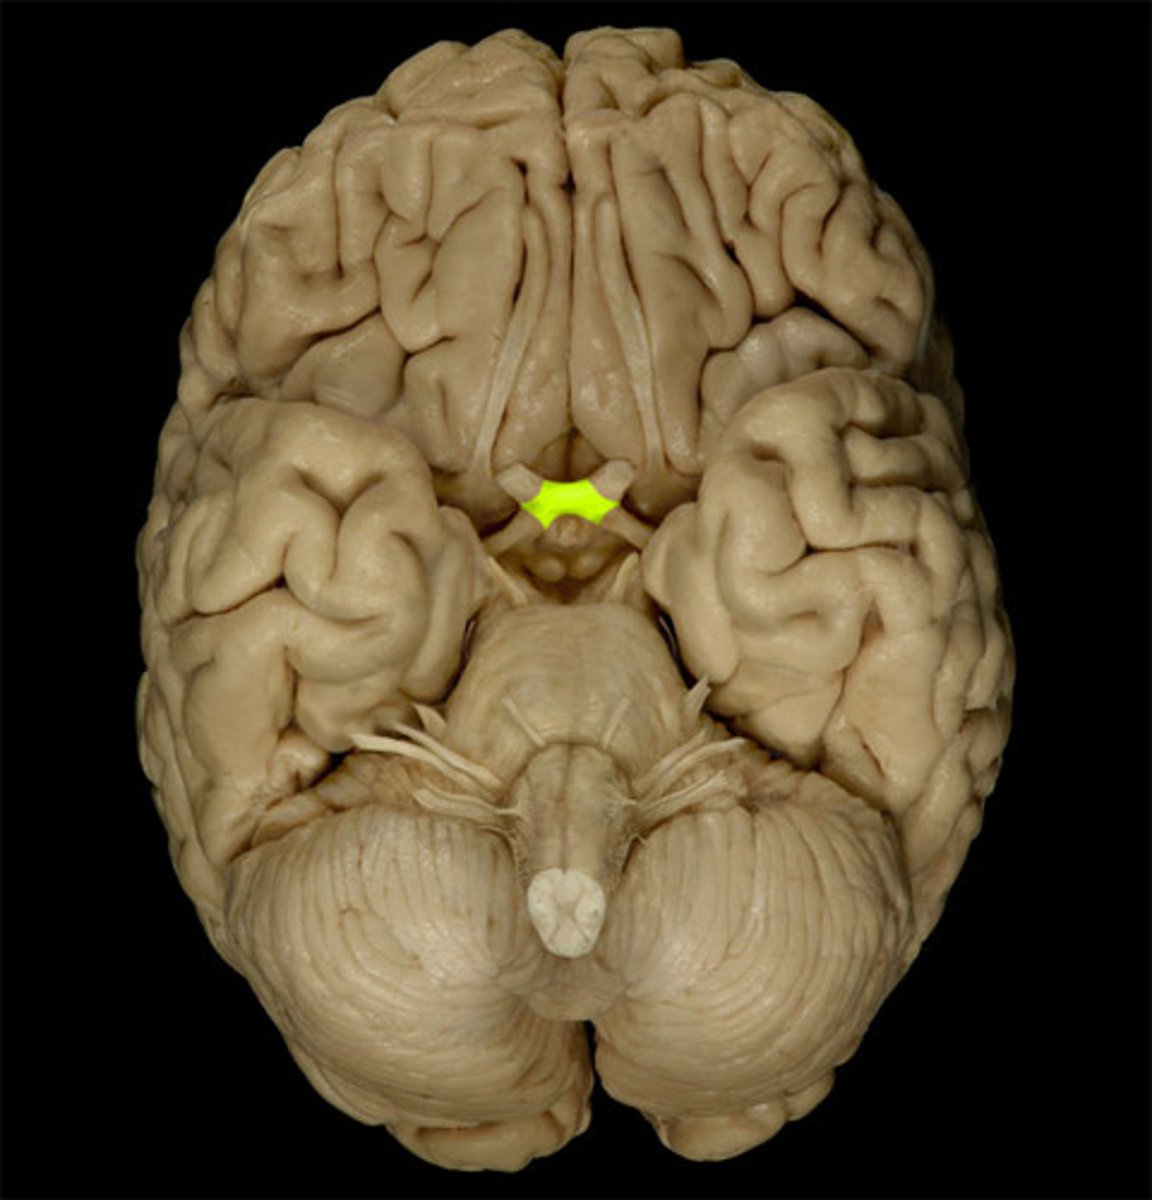

anterior commissure

White matter tract that crosses the third ventricle. Located just anterior to the thalamus. connects parts of the frontal+temporal lobes of the 2 hemispheres.